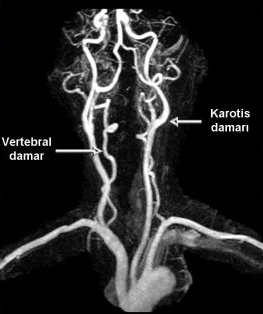

MR anjiografide, hasta tüp şeklinde büyük bir mıknatısın içine yatırılarak manyetik alan ve radyo dalgalarından yararlanılarak damarlar görüntülenir. Hastaya hiç ilaç vermeden bile damarlar görüntülenebilir, ancak son yıllarda kol toplardamarından ilaç verilmesi tercih edilmektedir. MR ile vücuttaki tüm damarlar görüntülenebilir. Özellikle ultrasonografinin iyi gösteremediği beyin, göğüs ve karın bölgesindeki damarlar da çok iyi incelenebilir. Ayrıca tüm damarlar üç boyutlu olarak istenilen açıdan değerlendirilebilir.

MR anjiografinin en önemli üstünlükleri vücuttaki tüm damarları hastaya radyasyon vermeksizin gösterebilmesidir. Günümüzde en çok beyin, boyun, bacak ve karın damarlarında kullanılır. En önemli dezavantajı vücudumuzdaki kalp, damar ve barsak gibi organların hareketleri nedeniyle “artefakt” adı verilen bazı yanıltıcı görüntülerin oluşmasıdır. Bu nedenle normal olan bazı damarları daralmış, daralmış bazı damarları da tam tıkalı gibi gösterebilir. Ayrıca damar duvarında kireçlenme ve vücutta bulunan metal parçaları görüntüyü bozabilir. Bazı durumlarda da atardamar ve toplardamarlar birbirlerinden ayrılamayabilirler. Bu yüzden MR anjiografi tıpkı renkli Doppler ultrasonografi gibi damar hastalıklarının görüntülenmesinde bir “ön test” olarak kullanılır. Bu ön testlerde bir anormallik saptanırsa genellikle BT anjiografi ve klasik anjiografi gibi yöntemlerle ileri inceleme yapılır.